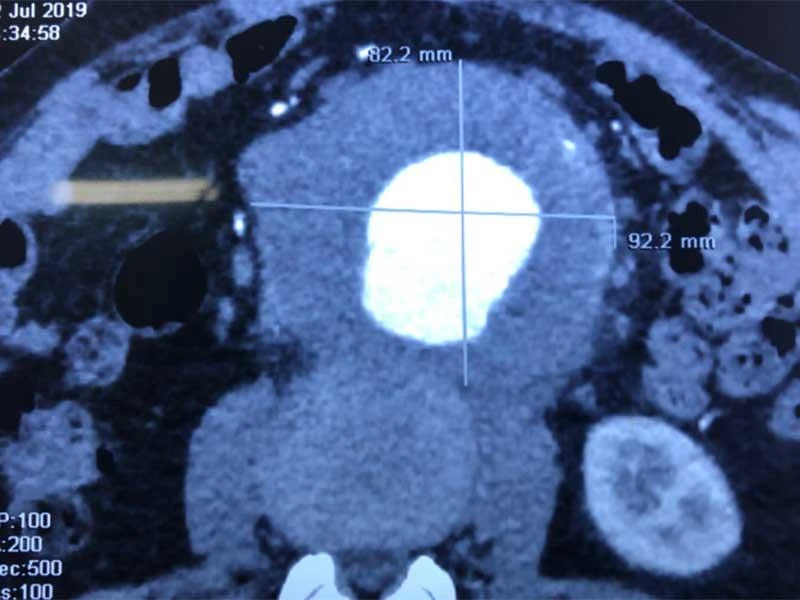

Tại đây, ông được chẩn đoán có túi phình kích thước 9 x 8,6 cm, như một trái bưởi nhỏ, nếu vỡ sẽ khiến một lượng lớn máu xòa ra trong ổ bụng, nguy cơ tử vong lên đến trên 90%. Sau hơn 2 giờ phẫu thuật, các bác sĩ đã loại bỏ trọn khối xơ vữa có trọng lượng 0,5 kg trong túi phình, đặt thành công ống ghép dacron (động mạch nhân tạo) vào động mạch chủ bụng thay thế cho đoạn bị phình giãn.

Hình ảnh siêu âm động mạch chủ bụng phình to như quả bưởi sắp vỡ của ông V. Ảnh do BV Bình Dân cung cấp